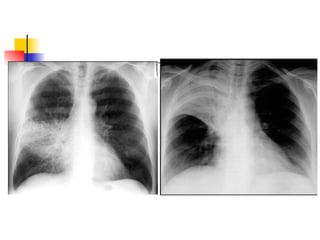

Describe what is shown on these

pts with alveolar shadowing!